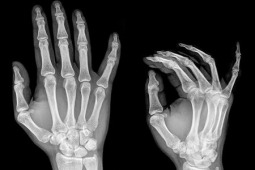

W badaniu uwzględniono dane 100 pacjentów (73 kobiety, średni wiek 51 lat) , u których występowały

niespecyficzne dolegliwości bólowe stawów oraz obecne były przeciwciała aCCP. W grupie tej u 50% rozpoznano zapalenie stawów(ZS), u większości w okresie pierwszych 12 miesięcy obserwacji (mediana okresu obserwacji do chwili rozpoznania zapalenia stawów- 7,9 miesięcy). Grupę chorych z zapaleniem stawów wyróżniały następujące parametry : czas trwania sztywności porannej ≥30 minut oraz bolesność przy palpacji drobnych stawów, ponadto w tej grupie stwierdzono tendencję do występowania czynnika RF i aCCP w wysokim mianie oraz dodatni wynik Power Doppler w ocenie ultrasonograficznej stawów.